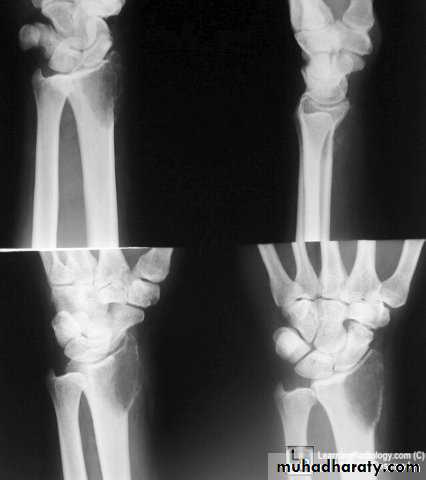

X-ray shows translucent cystic lesion in the metaphysis and shaft of bone with bone widening and cortical expansion and thinning with possible pathological fracture.It may show bridges of calcification inside as a result of healing of micro fractures that commonly occurs,

by this way it may gradually disappear and heals later in life;

X-ray shows well-defined irregular eccentric lucent lesion in the metaphysis that does not reach the articular surface, it may show ballooning, cortical widening and thinning.

Rarefied area of the bone end reaching just below the articular surface.Eccentric lesion with bone expansion and ballooning with cortical thinning, sometimes pathological fracture.

There may be calcific trabiculations inside the lesion giving it the commonly known saop-bubble appearance.